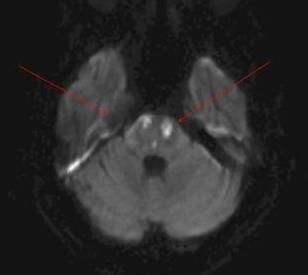

A 30-year-old woman with a history of hypertension, hyperlipidemia, diabetes, chronic kidney disease, and polysubstance abuse had a sudden change in mental status, weakness on her right side, slurring of speech, and new-onset dysphasia. Her blood pressure was 190/95 mm Hg. Brain DW-MRI showed patchy areas indicating increased signal in the pons on both sides; repeated DW-MRI showed a diffusion abnormality. She had a stroke attributed to hypertension caused by cocaine abuse.